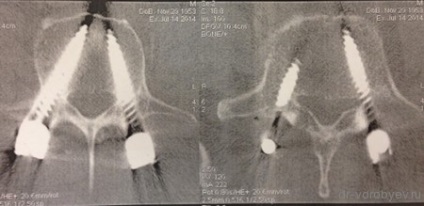

CT - ellenőrzése helyességét a csavar helyeket. Ők szigorúan a fogantyúk és lábak eléréséhez szinte az ellenkezője kérgi réteg.